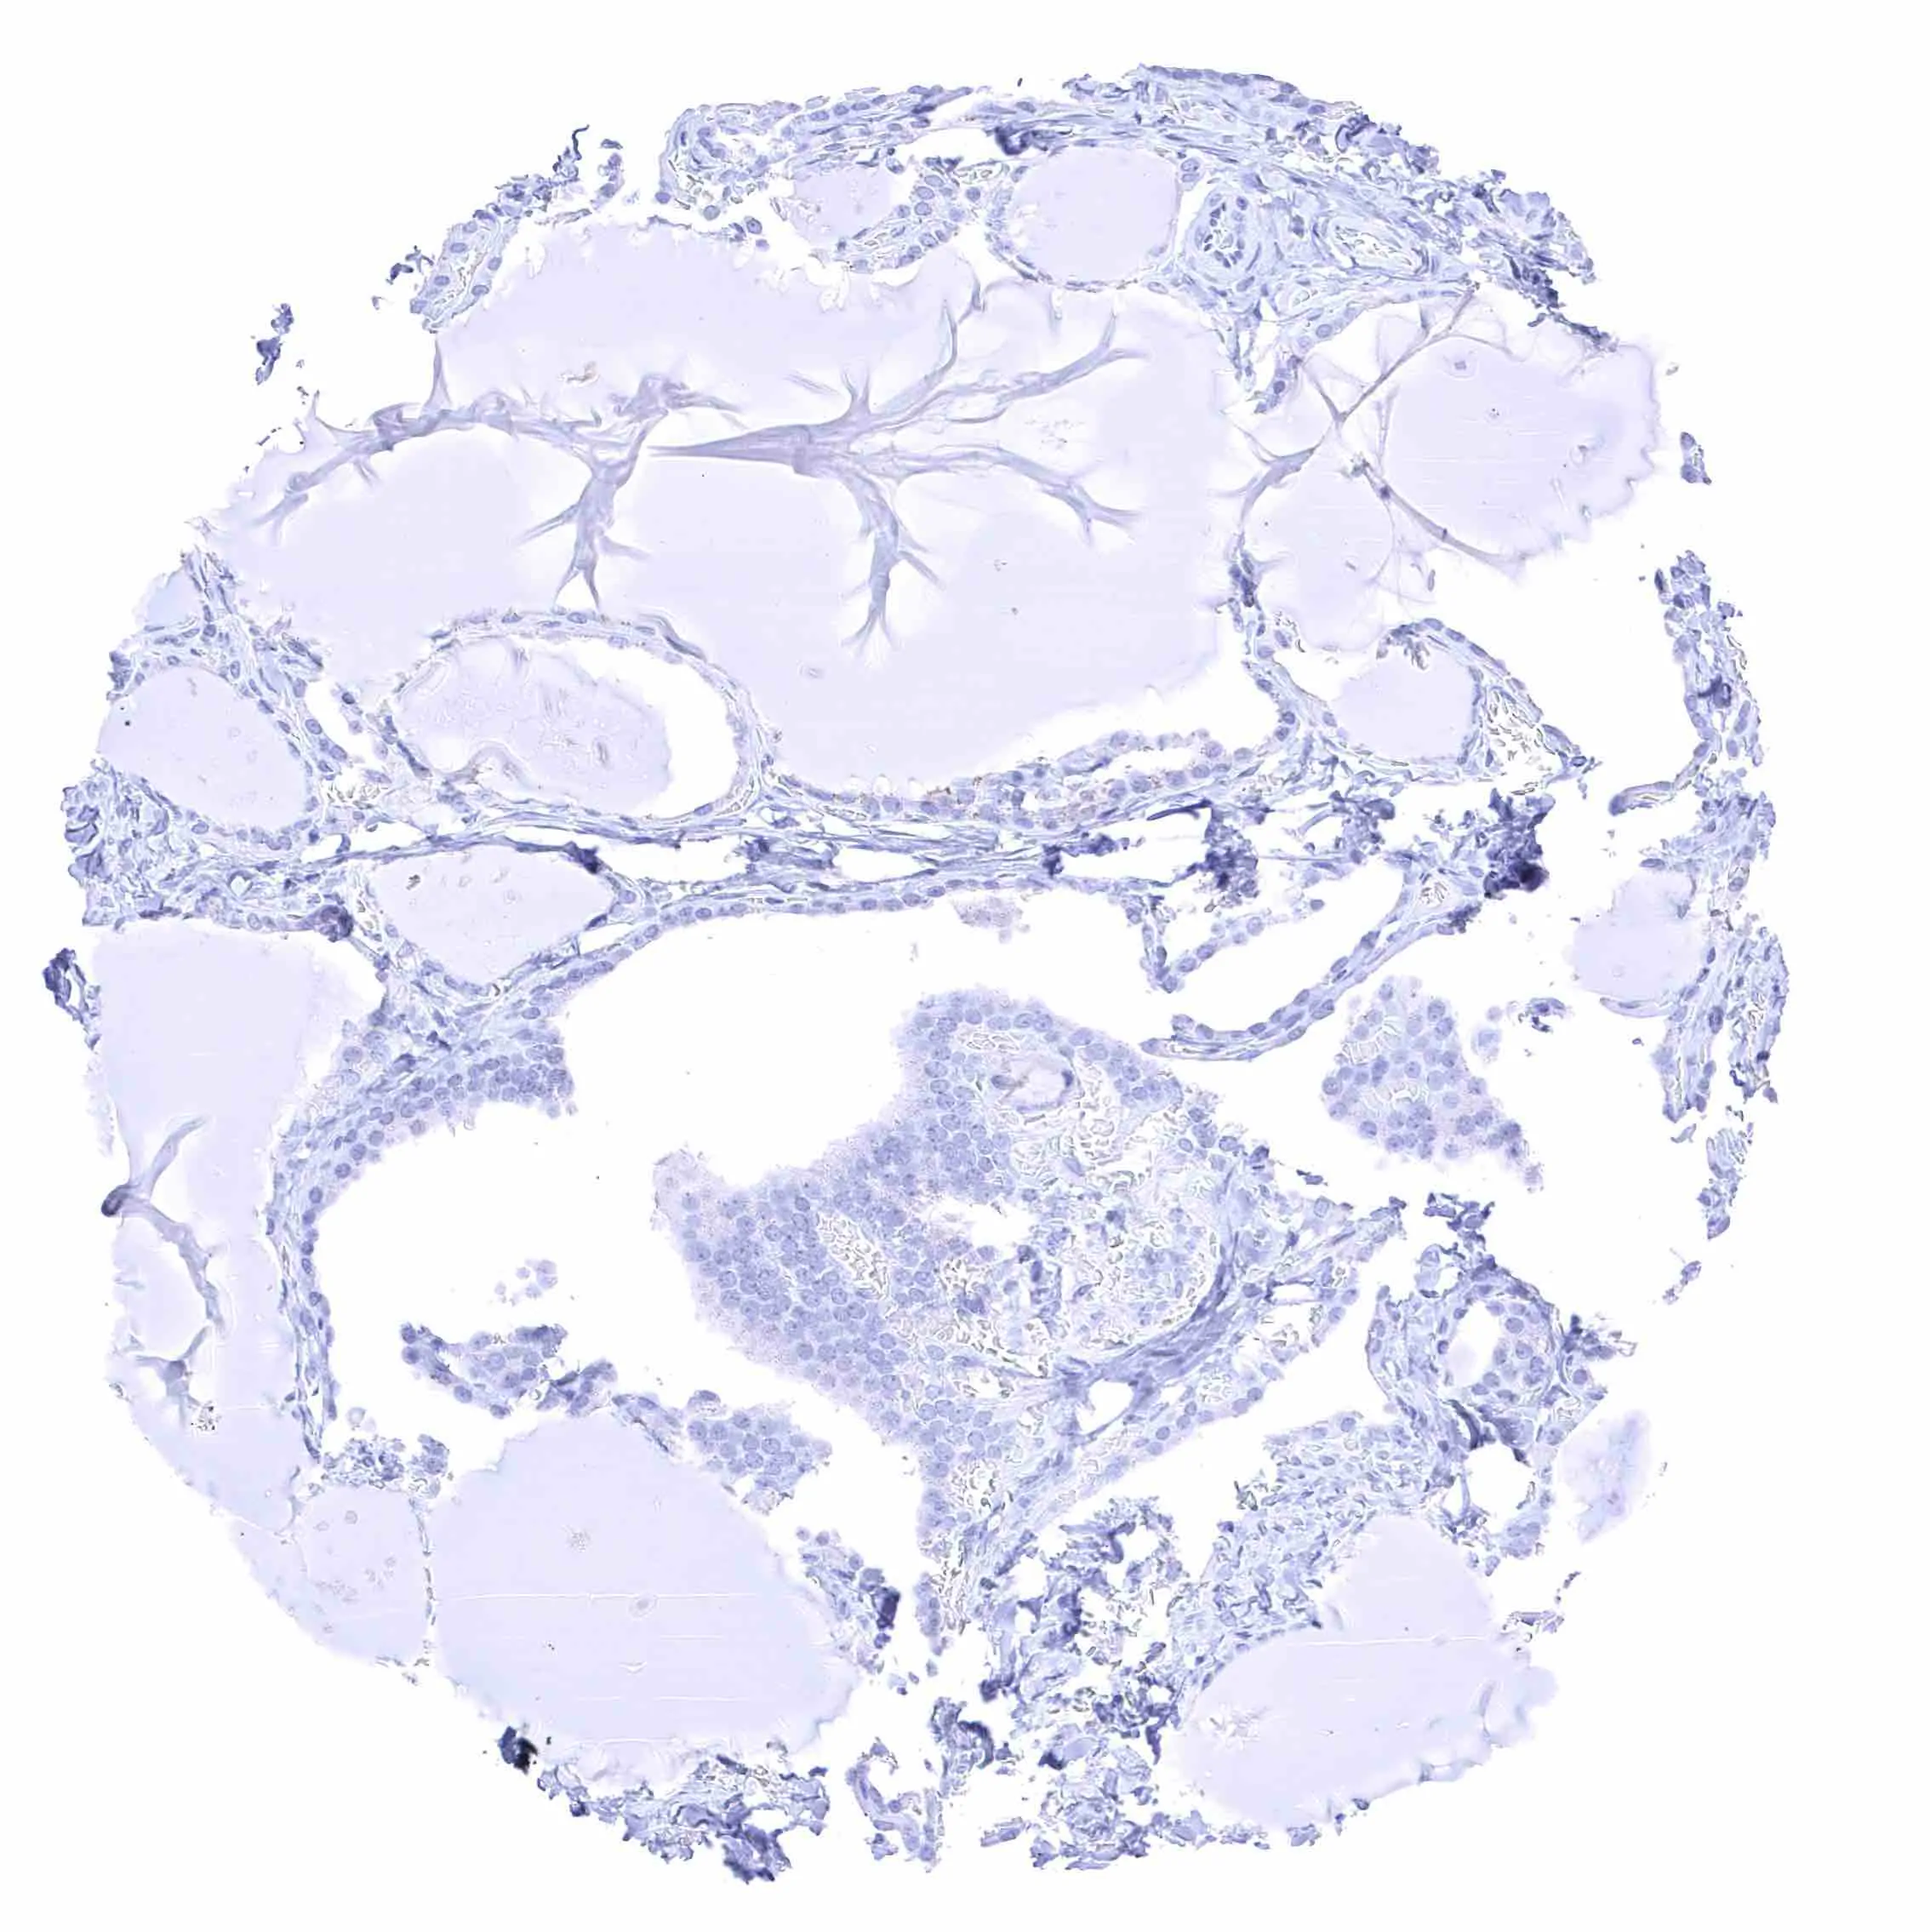

Lung